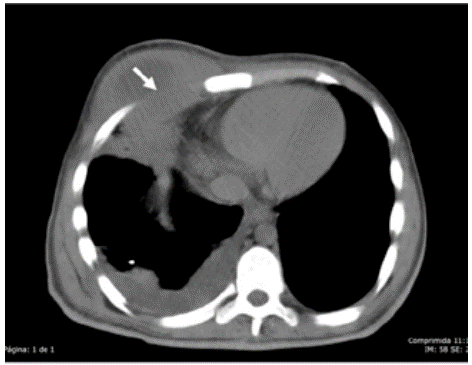

Computed tomography of the thorax was performed, revealing consolidation of the middle lobe and ipsilateral pleural effusion, along with hypodense mass projected on the pectoral muscular plane (Figure 1) and extension from the fourth to the seventh intercostal space, leading to diagnose empyema neccesitatis.

Computed tomography of the thorax. Axial section.

Figure 1: Computed tomography of the thorax. Axial section.

Figure 1 shows consolidation of the middle lobe and ipsilateral pleural effusion, along with hypodense mass projected on the pectoral muscular section. The arrow indicates the point where pleural collection passes through the muscular section of the chest wall into the subcutaneous cellular tissue of the right pectoral region.